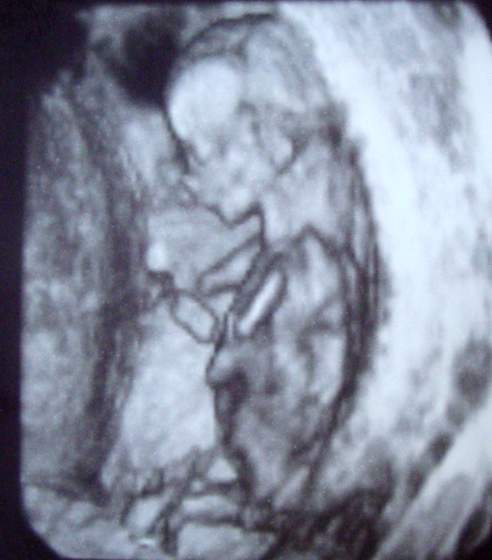

aia slicznoscichyba dziewczynka co?

Niesamowicie się cieszę! Sama jakoś gdzieś głęboko w sobie czułam, że to córcia